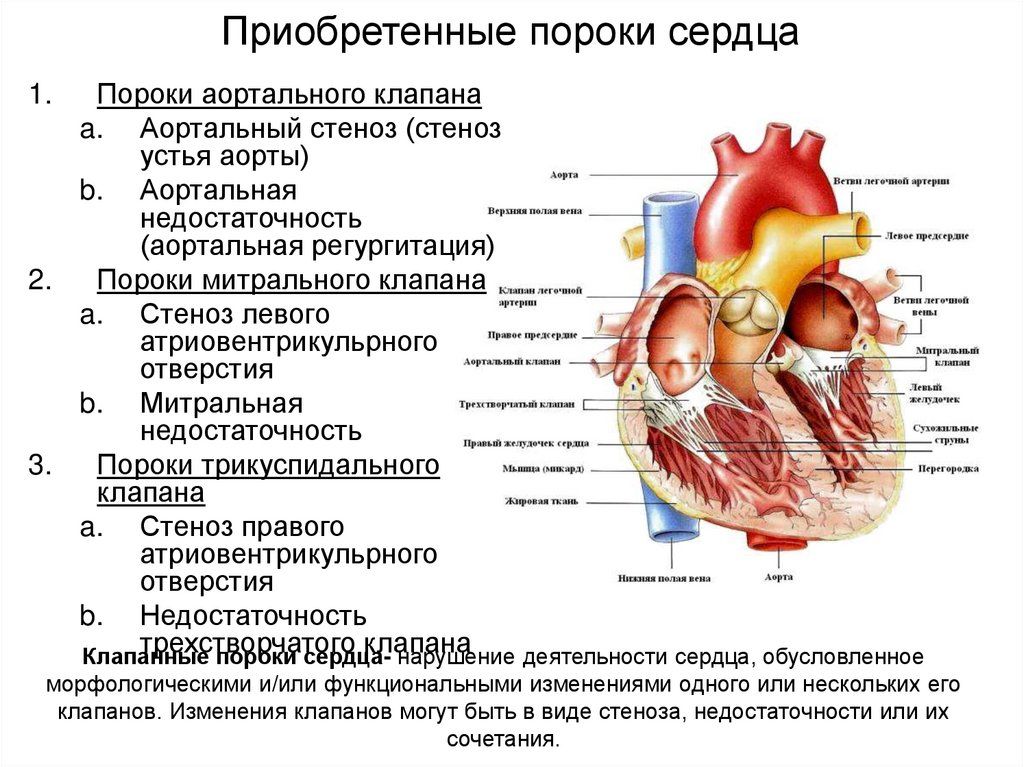

Пороки приобретенные

Приобретенные пороки сердца могут развиваться у взрослых и детей. Это дефекты одного или нескольких клапанов, поэтому их называют клапанными. Это может быть стеноз (сужение) или недостаточность клапанов, а также их сочетания. Имеющиеся дефекты препятствуют нормальному току крови. Развиваются приобретенные аномалии сердца в результате болезней, перегрузки или расширения сердечных камер. Этот порок может быть вызван воспалительными процессами, инфекционными заболеваниями и аутоиммунными реакциями.

Симптомы

Клинические проявления зависят от вида порока и его тяжести. Симптомы определяются локализацией (митральный, аортальный или трикуспидальный клапан) и количеством пораженных клапанов. Кроме этого, признаки зависят и от функциональной формы: стеноз, недостаточность, наличие стеноза или недостаточности на нескольких клапанах сердца, наличие и стеноза, и недостаточности на одном клапане.

Митральный стеноз

Характеризуется одышкой, возникающей в первое время только при нагрузках, а затем и в спокойном состоянии. Наблюдается сухой или влажный кашель, охриплость голоса, кровохарканье. Учащается сердцебиение, в работе сердца происходят перебои, отекают конечности. Пациенты жалуются на боли в груди и под ребрами справа. Больной испытывает слабость и усталость. В тяжелых случаях возможен отек легких и приступы астмы.

Митральная недостаточность

Сначала одышка присутствует только при физической нагрузке, через некоторое время появляется и в состоянии покоя. Больной жалуется на боли в сердце, слабость и сердцебиение. Возникает сухой или слегка влажный кашель. При обследовании обнаруживают шум в верхней части сердца, увеличение миокарда вверх и влево.

Аортальная недостаточность

Субъективные признаки такого порока могут долго не проявляться в связи с компенсацией за счет работы левого желудочка. Боль в сердце при аортальной недостаточности обычно плохо снимается или совсем не проходит после принятия нитроглицерина. Больные жалуются на головные боли, головокружение, одышку и боль в груди при нагрузках, а потом и в покое, сердцебиение, чувство тяжести и боль в подреберье справа. Наблюдается бледность кожных покровов, пульсация артерий шеи и головы, отеки ног, возможны обмороки.

Аортальный стеноз

Признаки такого порока могут не появляться длительное время. Типичные симптомы – это головная боль, головокружение, обмороки, одышка при нагрузках, боли в груди, обычно сжимающие. В дальнейшем появляются боли в подреберье справа, высокая утомляемость, отеки конечностей, одышка в покое, приступы астмы. Наблюдается бледность кожи, редкий пульс, повышенное или нормальное диастолическое давление и сниженное систолическое. Признаки аортального стеноза более выражены при физических и эмоциональных нагрузках.

Трикуспидальная недостаточность

Данный вид порока сердца в чистом виде развивается редко, обычно он сочетается с другими пороками клапана. При развитии трикуспидальной недостаточности возникают отеки, тяжесть в правом подреберье, возможен асцит. Кожа становится синюшной, может присутствовать желтоватый оттенок, наблюдается набухание и пульсация вен печени и шеи. Артериальное давление повышено, пульс учащенный. Может нарушаться работа печени, почек, желудочно-кишечного тракта.

Комбинированные пороки

Комбинированные пороки сердца более распространены, чем изолированные. При этом может быть поражен один клапан, два или три.

Возможны сочетанные пороки, при которых в одном клапане обнаруживается два дефекта: и стеноз, и недостаточность. Симптомы комбинированного порока сердца зависят от преобладания одного поражения над другим. В некоторых случаях признаки обоих дефектов выражены одинаково.

Наиболее часто наблюдается одновременный стеноз и недостаточность митрального клапана. Обычно преобладают симптомы какого-либо одного. Признаками такого порока в первую очередь являются одышка и синюшность кожных покровов. Если преобладает стеноз митрального клапана сердца, то отмечается малый пульс, повышенное диастолическое и пониженное систолическое давление. Если более выражена недостаточность, а не стеноз, то АД и пульс могут оставаться в норме.

Также в случае митрального порока, где преобладает стеноз, будут присутствовать признаки стеноза левого предсердно-желудочкового отверстия. Это одышка, кровохарканье, сердцебиение, сбои в работе сердца. Если более выражена митральная недостаточность, то среди симптомов будет наблюдаться боль в сердце, кашель сухой или с выделением небольшого количества мокроты.